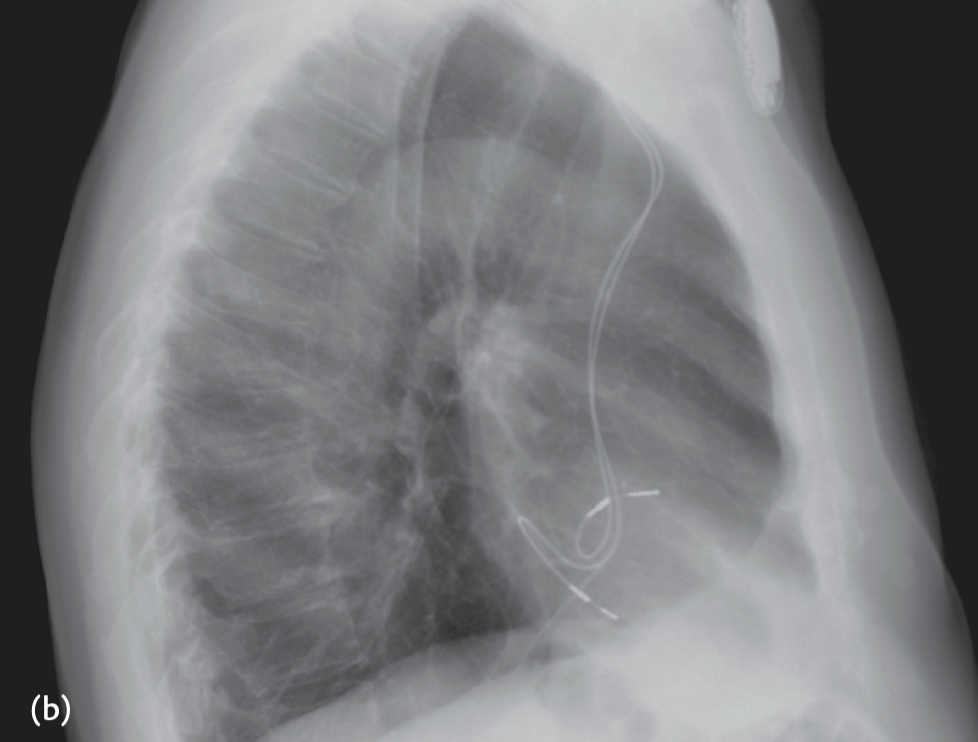

A 72-year-old patient was admitted for stroke. He had been implanted with a dual-chamber pacemaker 2 months ago for sinus dysfunction. Interrogation of the pacemaker was normal and did not disclose any atrial arrhythmias that may have explained the neurological event. A chest X-ray was performed and is shown

The ventricular lead is in the LV via a patent foramen ovale

• The PA view the ventricular lead would be expected in a lower position

• The lateral view shows the V lead to be posterior, whereas an RV lead would be anteriorly located.

• LV capture results in a negative QRS in lead I (which may be observed occasionally also with RV pacing) and an RBBB QRS morphology.